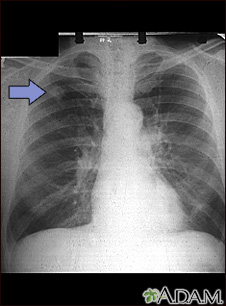

SCLC is the most aggressive form of lung cancer. It usually starts in the breathing tubes (bronchi) in the center of the chest. Although the cancer cells are small, they grow very quickly and create large tumors. These tumors often spread rapidly (metastasize) to other parts of the body, including the brain, liver, and bone.

SCLC has usually spread to other parts of your body by the time it is diagnosed.

- Chest x-ray

Usually, if a biopsy shows cancer, more imaging tests are done to find out the stage of the cancer. Stage means how big the tumor is and how far it has spread. SCLC is classified as either: